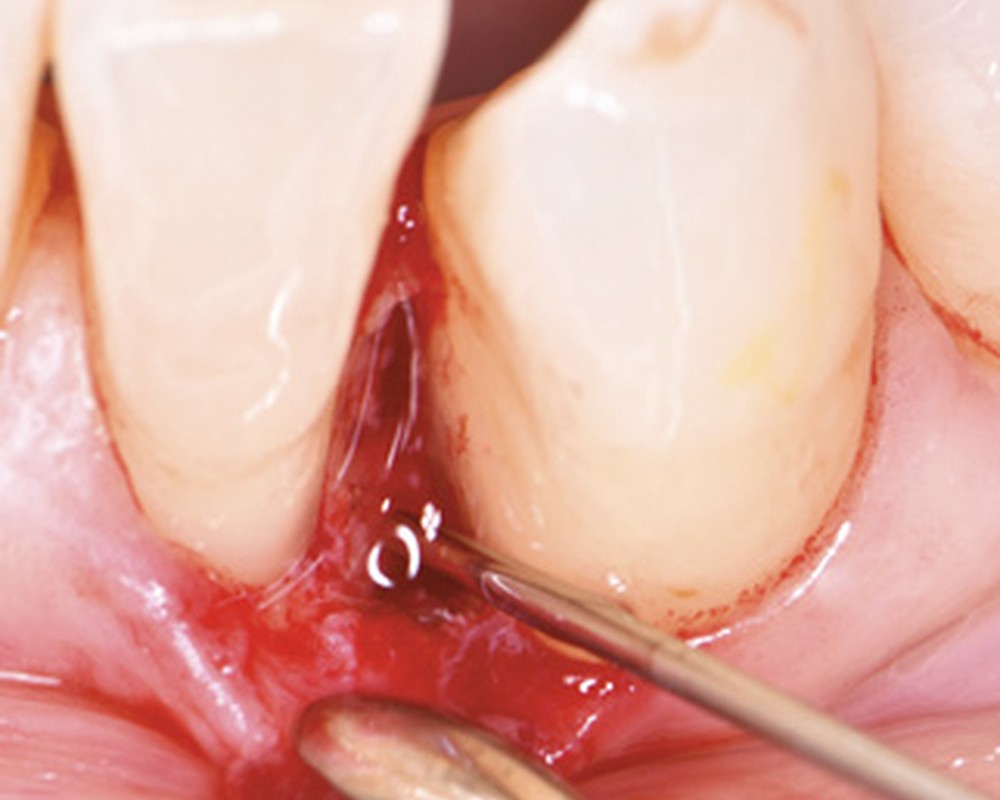

Ce cas clinique présentera une procédure de traitement chirurgical d’un défaut intra-osseux large et profond combinant un lambeau minimalement invasif à l’application de biomatériaux. Nous analyserons les facteurs ayant influencé la décision thérapeutique et le pronostic. L’approche réalisée a permis d’obtenir le comblement du défaut tout en évitant un effondrement tissulaire. Cette stratégie thérapeutique implique un diagnostic clinique et radiologique précis et une compliance exemplaire du patient. Les défauts intra-osseux profonds et larges peuvent bénéficier d’une approche régénératrice alliant un lambeau minimalement invasif à des biomatériaux.

Différentes techniques chirurgicales ont été progressivement proposées, avec pour objectifs de réduire le traumatisme chirurgical, d’augmenter la stabilité du lambeau et du caillot, de permettre une fermeture primaire de la plaie et de réduire le temps d’intervention. La réduction des suites postopératoires est aussi au cœur de ces techniques [3].

Parmi elles, l’approche régénérative des défauts intra-osseux a montré une réduction de la profondeur de poche parodontale et un gain d’attache clinique plus importants que le lambeau d’assainissement conventionnel sans régénération [4-6]. L’utilisation de biomatériaux (matériaux de substitution osseuse, membranes, dérivés de la matrice amélaire) a permis de repousser les indications de ces techniques et, par conséquent, de conserver des dents avec un pronostic réservé.